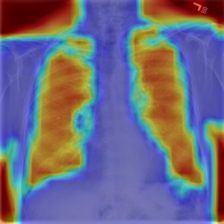

4.7.2 Activation Response Maps

As shown in Fig. 9, given the text lungs, we can find that the activation maps can accurately highlight the target regions. Therefore, we can achieve a higher performance on the downstream tasks. However, the activation maps are imperfect, as the background regions are also highlighted.